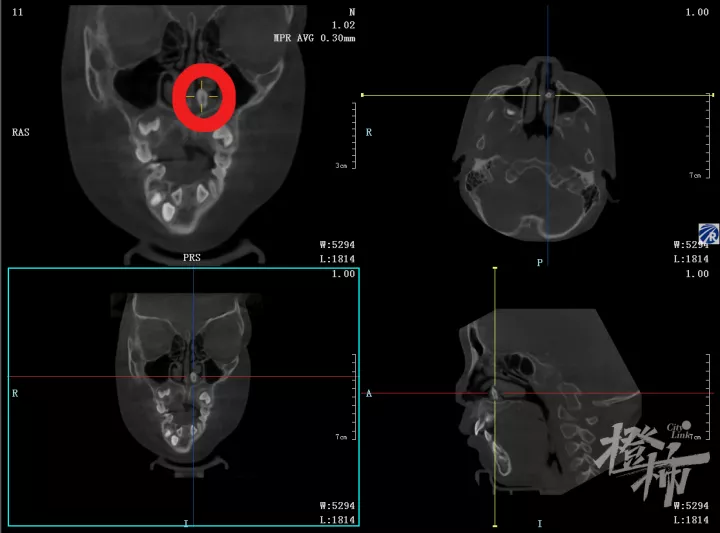

通过CT检查,医生发现茹茹上前牙区长了两颗多生牙,其中一颗确实已经跑到了鼻腔里。

进一步询问病史了解到,原来早在2年前茹茹就已经在其他医院拍片子发现了多生牙,但没有任何症状,当时医生已经建议手术拔除,但担心拔除多生牙的风险较大,茹茹妈妈选择了保守观察。而最近,茹茹妈妈发现茹茹的一颗大门牙长得越来越歪斜,再次去做了牙齿检查,这才发现多生牙不但把茹茹的门牙越顶越歪,而且其中一颗还深入到了鼻腔里。